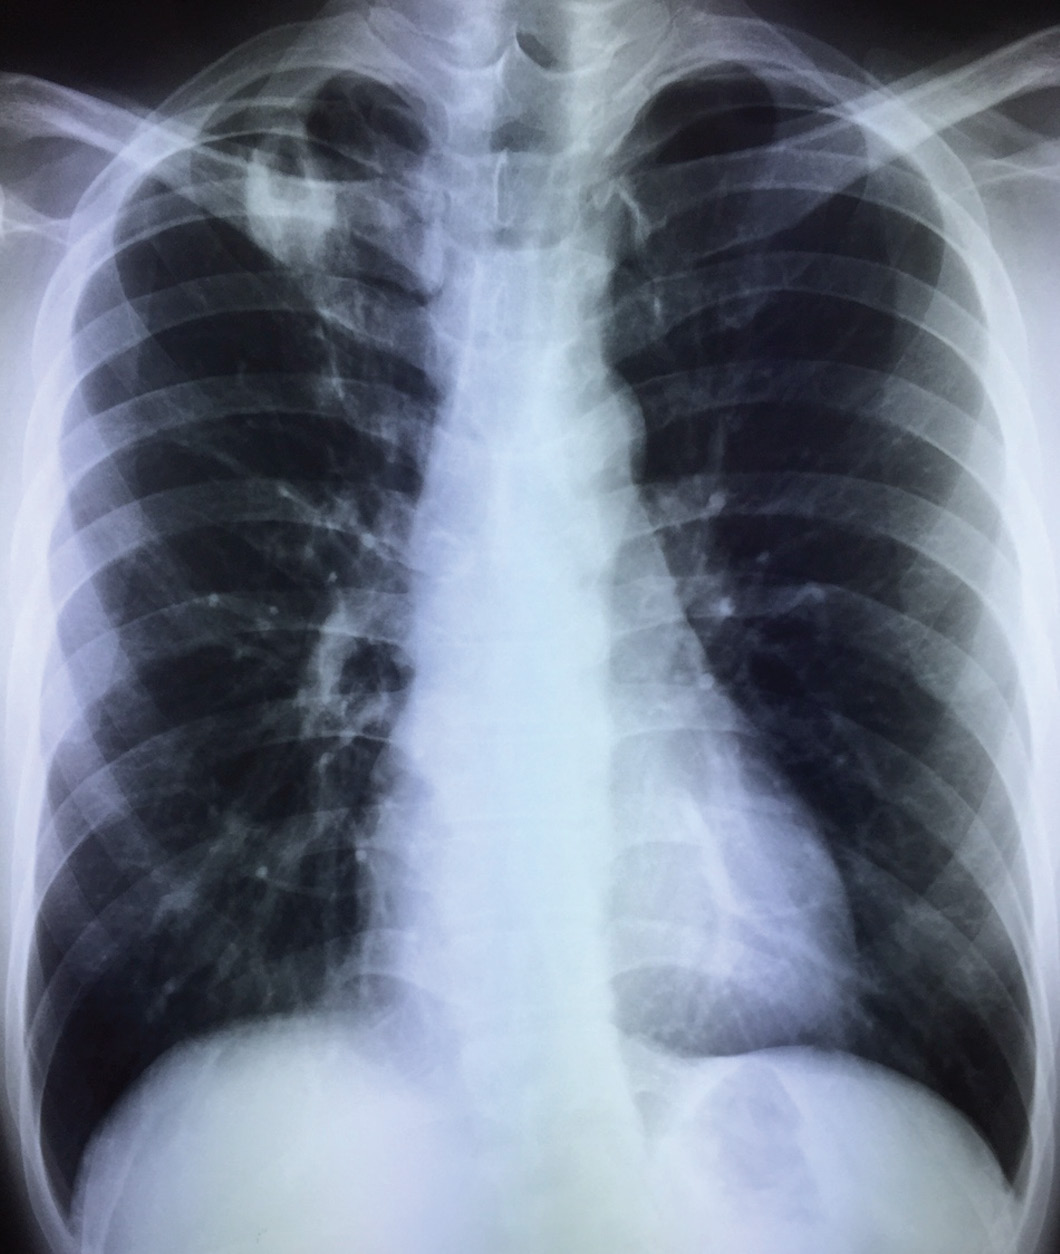

A young local man in his late 20’s, previously well, was found on pre-employment screening to have abnormal chest X-ray. He was otherwise asymptomatic.

He had started to develop a dry cough a week later, although he did not have any fever or other constitutional symptoms. A repeat chest X-ray showed progression of radiological changes.

The most likely diagnosis remains pulmonary tuberculosis despite the negative sputum smears and TB PCR, because of the radiological appearance, the lack of any major immunosuppressive condition, and the relatively high rates of tuberculosis locally. He is also not in the age group where cancer is likely. The conundrum is whether to further investigate or start therapy. “Watchful waiting” is not a good option as there has been obvious radiological progression. The issue with further investigation is that a more invasive procedure, such as bronchoscopy with bronchoalveolar lavage and possibly transbronchial lung biopsy, will be necessary, with its attendant risks. A CT thorax is unlikely to yield more information that will impact on a therapeutic decision. The issue with empirical TB therapy is, naturally, what if this is not TB?